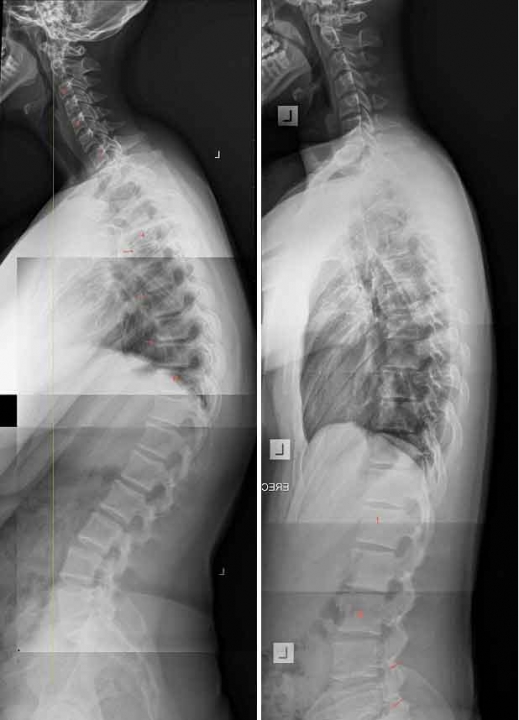

한 호주 의사가 과도한 스마트폰 사용으로 인해 목뼈가 휘어지는 증상인 이른바 ‘텍스트 넥’(text neck), 즉 '거북목 증후군'에 걸린 7살짜리 어린 환자의 X레이 사진을 공개해 사람들의 경각심을 불러일으키고 있다.

카터가 공개한 사진은 그의 병원을 찾은 수많은 텍스트 넥 환자 중 한 명이었던 어린이의 것으로, 치료 전 후의 목뼈 상태가 크게 대조되는 모습이 잘 드러나 있다.